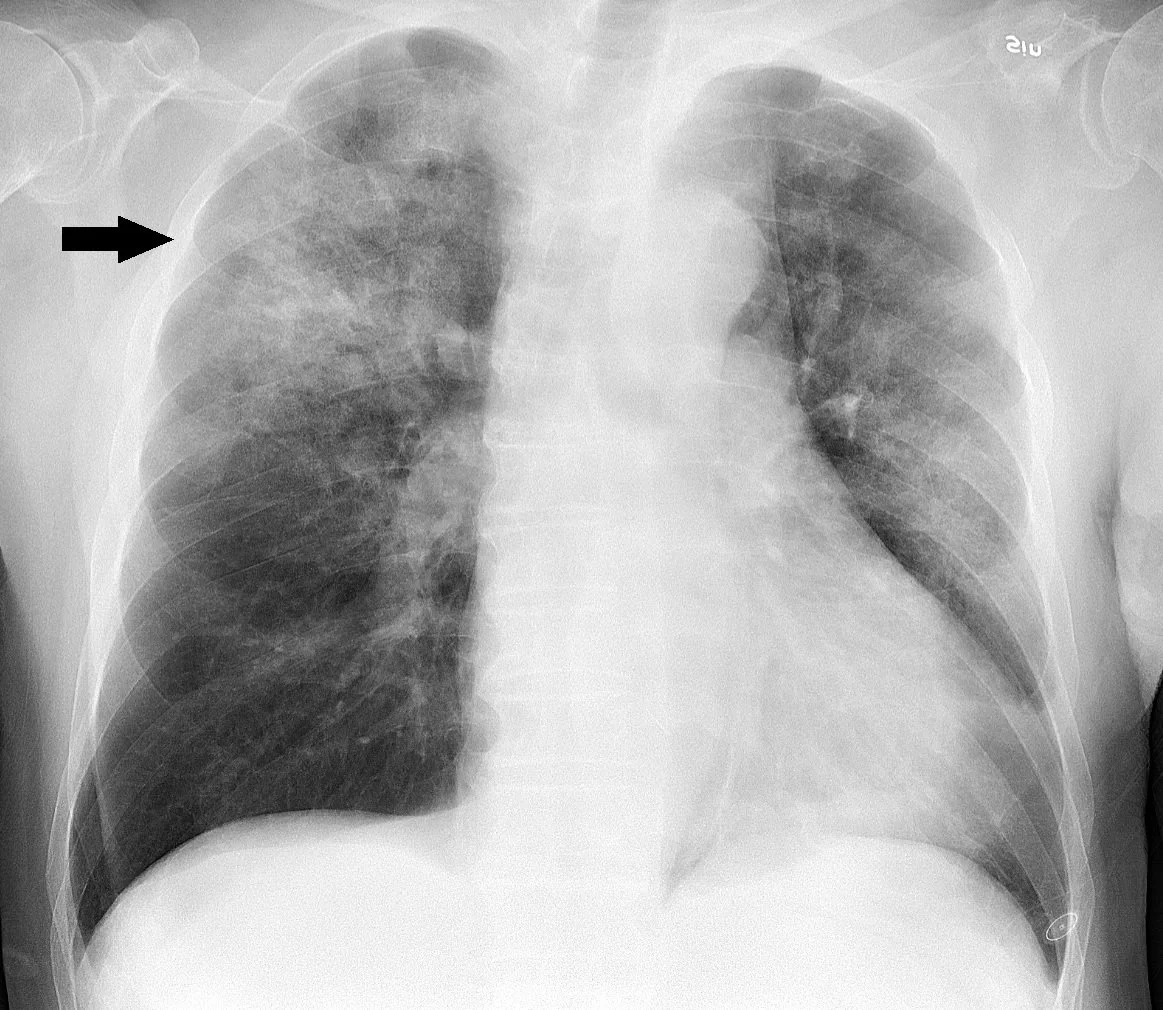

Community acquired pneumonia (commonly abbreviated to “CAP”) is a life-threatening lung infection and CAP is a leading cause of hospitalization and mortality globally.(1,2) It is defined by the presence of respiratory signs and symptoms (cough, sputum production, dyspnea, chest pain), systematic effects (fever, fatigue, diaphoresis, headache, nausea, myalgias), and a new radiographic (chest x-ray) pulmonary infiltrate (See figure 1). A universal diagnostic definition of CAP does not exist.(3)